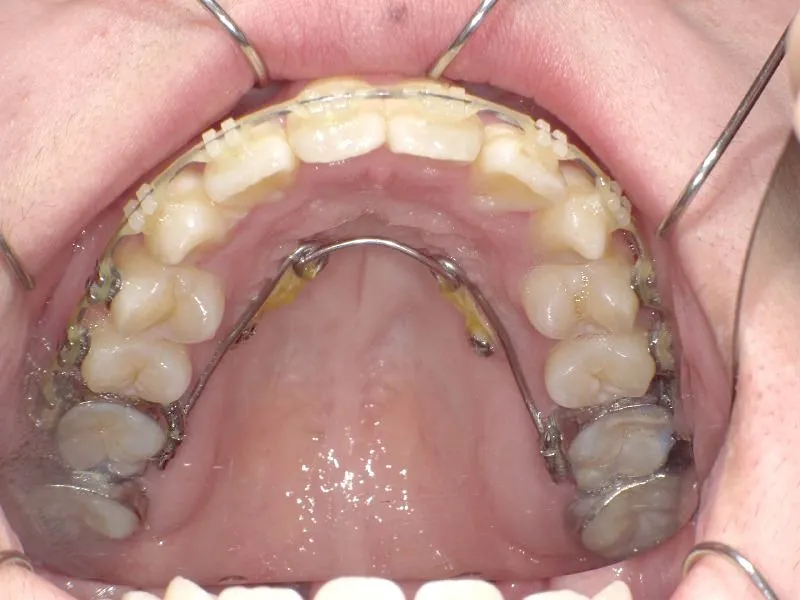

治療経過1

診断名 叢生・交叉咬合 装置名

矯正用アンカースクリュー4本・マルチブラケット矯正装置

抜歯の有無 非抜歯 治療期間・通院回数 3年 1ヶ月 / 42回